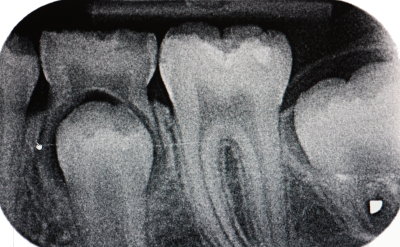

In den engen Zwischenräumen und unter allen Füllungen kann oftmals trotz Licht und Spiegel Karies nicht erkannt werden. Deshalb benötigen wir Röntgenbilder, um einen vollständigen Befund erstellen zu können. Durch die Röntgenbilder können schon beginnende kariöse Defekte rechtzeitig erkannt werden, so dass sie noch mit kleinen Füllungen versorgt werden können.

In unserer Praxis verwenden wir ausschließlich digitales Röntgen, wodurch die Strahlenbelastung um ca. 90 % reduziert wird.